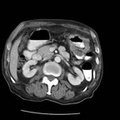

RADIOLOGY: GASTROINTESTINAL: GI: Case# 33875: ADENOCARCINOMA; ADENOPATHY IN THE GASTROHEPATIC LIGAMENT AS WELL AS LEFT CELIAC AXIS CHAINS. This is a 79-year-old male who had a barium enema on 8/21/97 demonstrating an area of narrowing and irregularity in the distal transverse colon just before the ascent for the splenic flexure. 1. Markedly thickened gastric wall consistent with biopsy result of adenocarcinoma. Adenopathy is suspected in the gastrohepatic ligament as well as left celiac axis chains. 2. Distal transverse colonic wall thickening immediately adjacent to the gastric wall thickening raises the possibility of spread of the adenocarcinoma to the colon. 3. Four small hepatic hypodensities, indeterminate at this small size. However, metastasis cannot be excluded. 4. Questionable L5 lytic lesion.